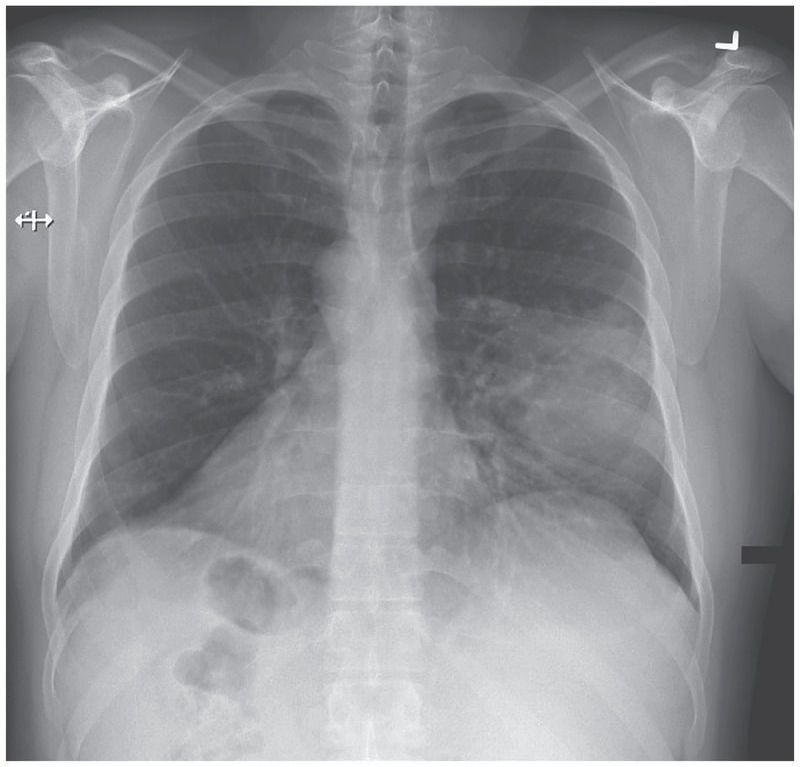

A 34-year-old man presented to the emergency department with a 5-day history of fever, cough, and dyspnea. He had received a diagnosis of situs inversus when he was 2 years of age, after a chest radiograph had been obtained in order to evaluate a cough. Physical examination was notable for heart sounds in the right side of his chest and for crackles in the middle field of the left lung. Radiography of the chest revealed a cardiac apex, aortic arch, and gastric bubble in the right side of the body and a lobar infiltrate in the left lung. A left-middle-lobe pneumonia was diagnosed. The patient reported that he had had chronic cough and recurrent sinusitis since childhood, and he also reported infertility — conditions that suggest a diagnosis of Kartagener’s syndrome, which is characterized by situs inversus, recurrent sinusitis, and bronchiectasis (which was not seen on his chest radiograph). This syndrome is a form of primary ciliary dyskinesia, an autosomal recessive condition that is caused by mutations in genes encoding ciliary components, resulting in abnormal motility of sperm-cell flagella and of cilia lining the respiratory tract and fallopian tubes. Primary ciliary dyskinesia also affects organ lateralization during embryogenesis, resulting in situs inversus in approximately half the cases. The patient was treated with moxifloxacin, and his pneumonia resolved completely. He received pneumococcal and influenza vaccines and was referred to the pulmonology service for follow-up. At last follow-up, 7 months after the initial presentation, the patient was doing well.